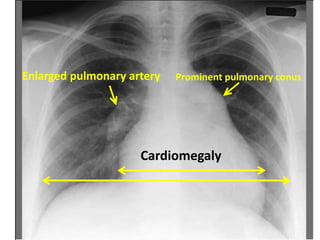

Pulmonary hypertension

Prominent pulmonary conus

Enlarged pulmonary artery

Cardiomegaly

Enlarged pulmonary arteries